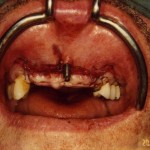

Lang zurückliegende Zahnverluste mit erheblichem Knochenkammschwund bedürfen einer Knochenaufbauenden Rekonstruktion vor einer Implantation oder auch zeitgleich kombiniert:

Gesteuerter Knochenaufbau bei Implantation (GBR):

Knochenspäne/Granulat/Membran.

Hierbei werden an die Stelle, wo Knochen fehlt, Knochenspäne aufgetragen und anschließend mit einem Titangitter oder einer Membran abgedeckt.

Die Knochenspäne können eigener Knochen (autogen) sein, der zerkleinert wird, oder sie bestehen aus tierischem (xenogen) oder künstlichem (alloplastischem) Material.

Die anschließend zur Abdeckung aufgebrachte Membran sorgt in erster Linie dafür, daß nicht schneller wachsende Bindegewebs- oder Epithelzellen die langsamer wachsenden Knochenzellen bei der Bildung von neuem Knochen stören.